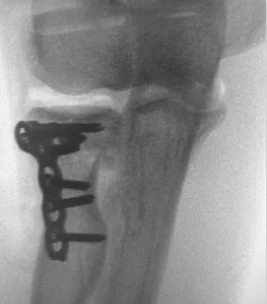

- Management if the fracture involves more than 33% of the articular surface or is sever displaced

- Surgical treatment:

- ORIF if possible

- Radial head Replacement if comminuted /inoperable

Intra-articular Distal Radius Fracture

- treated by anatomical open reduction, internal fixation and early mobilization